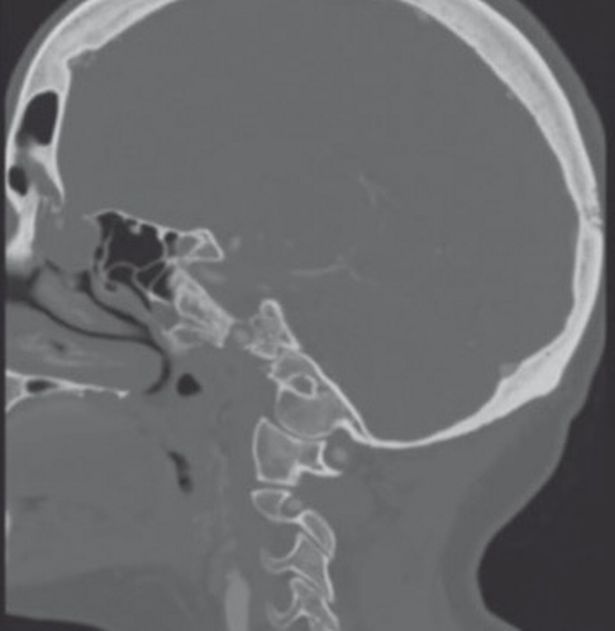

Προφανώς, εκείνος που έκανε το τεστ έβαλε την ειδική μπατονέτα πάρα πολύ βαθιά με αποτέλεσμα να δημιουργήσει μια μικρή τρύπα στον εγκέφαλο της άτυχης γυναίκας.

Οι γιατροί σε μια προσπάθεια να καταλάβουν τι ακριβώς συμβαίνει έβαλαν μια μικροκάμερα στη μύτη και ανακάλυψαν την τρομακτική αλήθεια.

Τα οστά του κρανίου στο σημείο εκείνο ήταν σπάσει ελαφρώς με αποτέλεσμα τα εγκεφαλικά υγρά να τρέχουν στην μύτη.